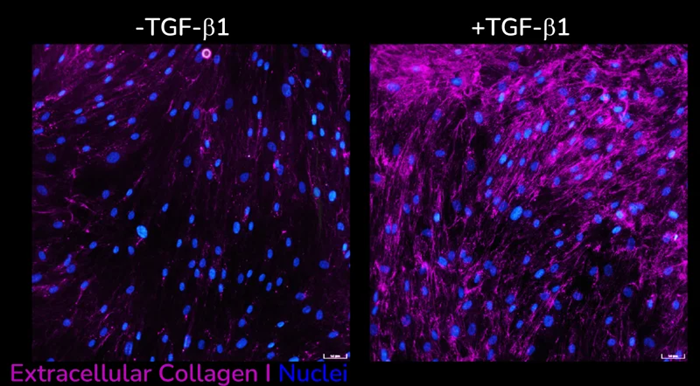

- Increased extracellular collagen I deposition

Extracellular collagen I deposition in response to dose-dependent treatment with TGF-β1. Images were acquired using the ImageXpress Confocal HT.ai imaging system. Image Credit: Newcells Biotech

Extracellular collagen I deposition without (left) and with (right) following TGF-β1 stimulation of primary HLFs acquired using ImageXpress Confocal HT.ai imaging system, Scale bar: 50 µM. Image Credit: Newcells Biotech